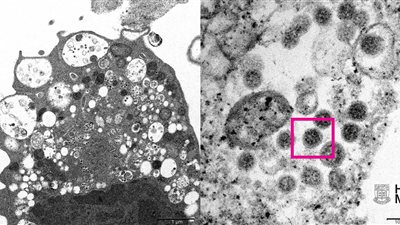

وكانت أصدرت جامعة هونج كونج، اليوم الأربعاء، أول صورة لمتحور فيروس كورونا "أوميكرون"، والتي تم التقاطها بالمجهر الإلكتروني "الميكروسكوب".

ووفقا لوكالة "سبوتنيك انترناشونال"، تمكن علماء الطب، بما في ذلك علماء الأمراض وعلماء الفيروسات، من أخذ صورة مجهرية إلكترونية لخلية كلية قرد (Vero E6) بعد الإصابة بالمتحور "أوميكرون".

وأصدرت الجامعة الصور بتكبير منخفض وعال وأوضح الباحثون أنه عند التكبير المنخفض، أظهرت الصورة المجهرية تلفا في الخلايا ذات الحويصلات المنتفخة التي تحتوي على جزيئات فيروسية سوداء صغيرة. فيما أظهر الرسم المجهري الضوئي العالي التكبير تكتلات من الجسيمات الفيروسية ذات أشواك إكليلية على سطحها.